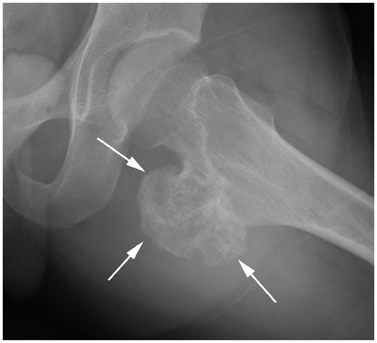

Systematic Approach of Sclerotic Bone Lesions Basis on Imaging Findings

- Sclerotic bone lesions are common, but there are diverse groups of tumors and non-tumorous lesions. Although plain radiograph and computed tomography can reveal important characteristics of these lesions, diagnosis is often challenging for radiologists. A systematic approach and familiarity with the imaging features of various sclerotic bone lesions may be greatly helpful for eliminating in the differential diagnosis. This review describes the systematic approach to diagnosing sclerotic bone lesions based on imaging findings.